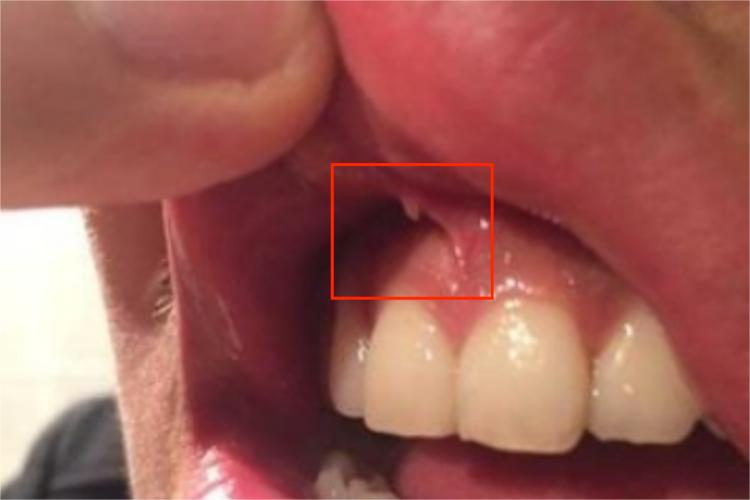

上唇系带正常情况下位于上唇内侧的前庭沟正中线上的小皱襞,相当于中切牙近中交界线的延长线上。上唇系带断裂,大部分患者的症状较轻,可以自行愈合,自愈后可能不会有明显的异常情况,但少数患者的断裂情况较为严重,若不经过治疗,自愈后可能出现上唇系带的位置改变。

上唇系带不易断裂,若上唇系带断裂主要为外力作用于唇部或上颌部所致,如玩闹中磕碰到上唇、过度撕扯上唇等不当方式。此外,上唇系带先天过短、附着位置较低也容易导致上唇系带断裂。

上唇系带断裂若症状较轻,避免继发感染后即可逐渐自愈。若上唇系带断裂较为严重,需由医生进行局部缝合或行唇系带成形术治疗,以避免出现上唇系带的位置改变等情况。